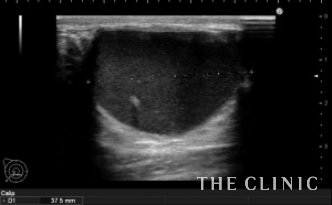

両胸に大きなヒアルロン酸のしこりがありました。

溶解、吸引後です。

黒く見えるヒアルロン酸はなくなりました。